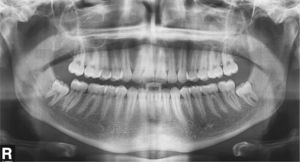

El paciente se presentó en nuestro centro con el siguiente cuadro: dentición permanente con proinclinación de dientes anteriores y desviación de la línea media, diente 53 persistente, dientes 13 y 23 elevados y desplazados hacia vestibular, curva de Spee marcada con extrusión del sector anteroinferior, dientes rotados y apiñados en maxilar y mandíbula, clase II de Angle con un resalte de 4mm y sobremordida de 0mm, además de ausencia de guía canina (figs. 13a a 13c y 14a a 14e).

El plan de tratamiento incluyó el establecimiento de una clase I de Angle con sobremordida horizontal y vertical fisiológicas mediante la distalización del sector posterosuperior, con corrección de los caninos superiores y aseguramiento de una guía canina. Las arcadas se dotaron además de una apariencia armoniosa eliminando la giroversión y los apiñamientos mediante la reducción del esmalte interproximal y el ajuste de las líneas medias. El paciente optó por un tratamiento con el sistema Invisalign alternativo a la aparatología fija con brackets. Se colocó un atache rectangular vertical en los dientes 13 y 23 y, en el curso del tratamiento, también en los dientes anterosuperiores y en el diente 43. Además durante todo el tratamiento el paciente llevó elásticos de clase II en ambos lados, del diente 14 al diente 46 y del diente 24 al diente 36 para obtener el anclaje necesario durante la distalización. La figura 15 muestra la situación intraoral de un caso similar con brackets en los dientes 13 y 46. En la zona de los brackets se acortó el alineador. Además de los alineadores se utilizaron elásticos de clase II del diente 13 al diente 46.

La situación intraoral después de finalizar el tratamiento (figs. 16a a 16e) muestra, como lo hacen los modelos montados en relación céntrica (figs. 17a a 17e), una clase I de Angle con relación intermaxilar anterior fisiológica y una guía canina asegurada. En la radiografía panorámica final no se observan signos patológicos; se indicó la extracción de los terceros molares inferiores (fig. 18). El paciente utilizó férulas de Imprelon durante la noche como sistema de retención (Scheu-Dental, Iserlohn).